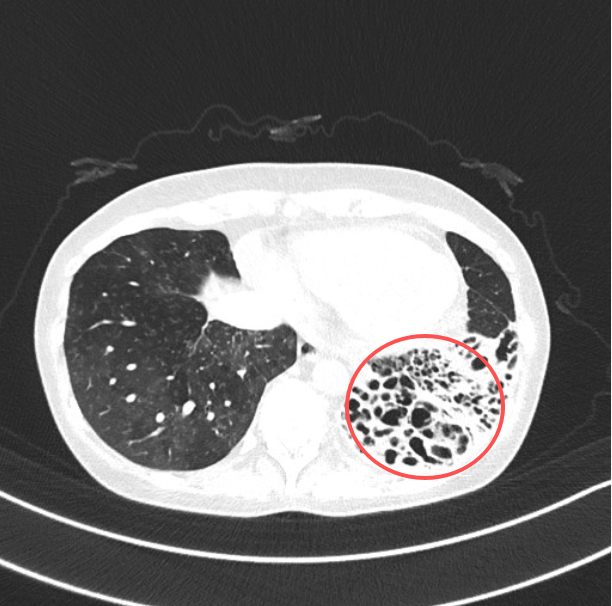

当她被推进北大深圳医院急诊大厅时,急诊科立即启动急危重症孕产妇绿色通道,值班急诊医生快速评估,患者的血压已接近休克阈值,心率100次/分,血氧饱和度95%,CT显示左下肺、左上肺舌段、右中肺支气管扩张。

胸外科团队沿右侧第5肋间开了一个七八公分的小口,胸腔镜探入后,快速吸净胸腔积血,刘继先主任精准找到出血点,“左下肺血管畸形得厉害,还有几个溃疡灶在渗血,必须尽快切除病变肺叶。”